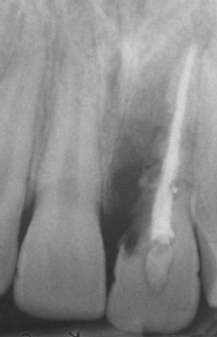

Analise a radiografia periapical a seguir:

Disponível em: Livro – Cirurgia Patologia Oral e Maxilofacial – Neville; Damn; Allen; & Bouquot. 3ª ed.

Assinale a alternativa que corresponde corretamente à condição apresentada pelo elemento dental 21.